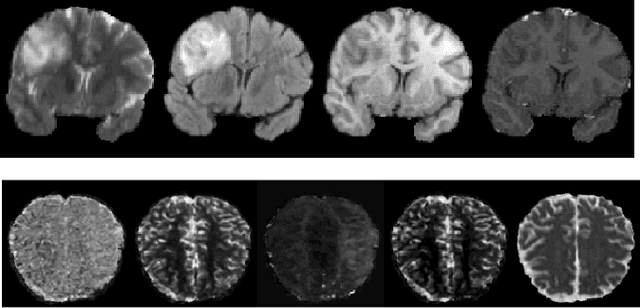

Abstract:Magnetic Resonance Imaging (MRI) of the brain can come in the form of different modalities such as T1-weighted and Fluid Attenuated Inversion Recovery (FLAIR) which has been used to investigate a wide range of neurological disorders. Current state-of-the-art models for brain tissue segmentation and disease classification require multiple modalities for training and inference. However, the acquisition of all of these modalities are expensive, time-consuming, inconvenient and the required modalities are often not available. As a result, these datasets contain large amounts of \emph{unpaired} data, where examples in the dataset do not contain all modalities. On the other hand, there is smaller fraction of examples that contain all modalities (\emph{paired} data) and furthermore each modality is high dimensional when compared to number of datapoints. In this work, we develop a method to address these issues with semi-supervised learning in translating between two neuroimaging modalities. Our proposed model, Semi-Supervised Adversarial CycleGAN (SSA-CGAN), uses an adversarial loss to learn from \emph{unpaired} data points, cycle loss to enforce consistent reconstructions of the mappings and another adversarial loss to take advantage of \emph{paired} data points. Our experiments demonstrate that our proposed framework produces an improvement in reconstruction error and reduced variance for the pairwise translation of multiple modalities and is more robust to thermal noise when compared to existing methods.